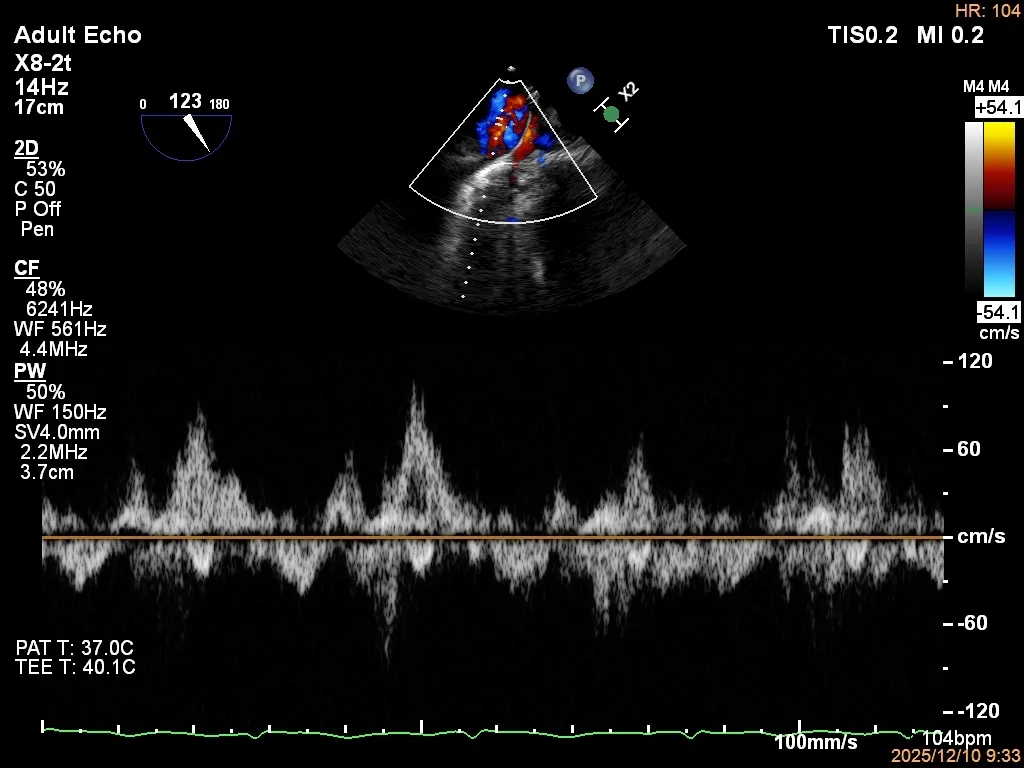

反流程度:极重度(5+),PISA法估测EROA约1.12cm²,R-VOL约98ml;

病变情况:P2-部分P3,脱垂宽度约27mm ,连枷间距11-13mm,瓣口面积7.8cm²,PML约25mm

其他:TR(重度) ,间接估测PASP约65mmHg;

3D-TEE二尖瓣相关解剖学参数:后叶长度:22-25mm,前叶长度:31-34mm;瓣环AP径:47mm,ML径:48mm;瓣口面积:约7.8cm²;脱垂宽度:30mm,最大连枷间距:14mm。

四条肺静脉均可测及收缩期反向血流